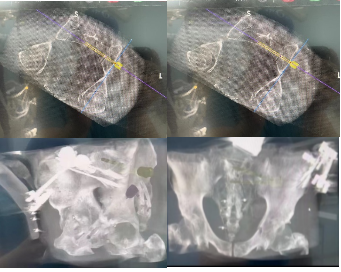

手术当天,骨科治疗组组长何罕亮副主任团队先采用我院先前引进的二代O臂机,现场拍摄患者的骨盆图像,上传至骨科机器人电脑中,经过机器人精密处理,患者的骨折三维图像直观地呈现在了所有人面前。随后,何主任根据图像,实时进行手术规划,选择最佳置钉通道。手术方案规划完毕后,手术机器人机械臂根据制定好的路线精准定位,将误差控制在1mm之内,医生不必切大切口,只需通过3个几毫米的切口便可将螺钉精准打入狭长的耻骨中,如此一来也不会损伤重要的血管神经组织。一旦通道确定,整个置钉过程不过短短几分钟,手术出血不足10ml,精准的置钉操作让医生不必担心需要反复调整而导致钉道松动。术后透视确认了螺钉位置准确无误,手术圆满成功,病人术后恢复满意。

机器人术中规划髋臼前柱螺钉&骨盆骶髂螺钉